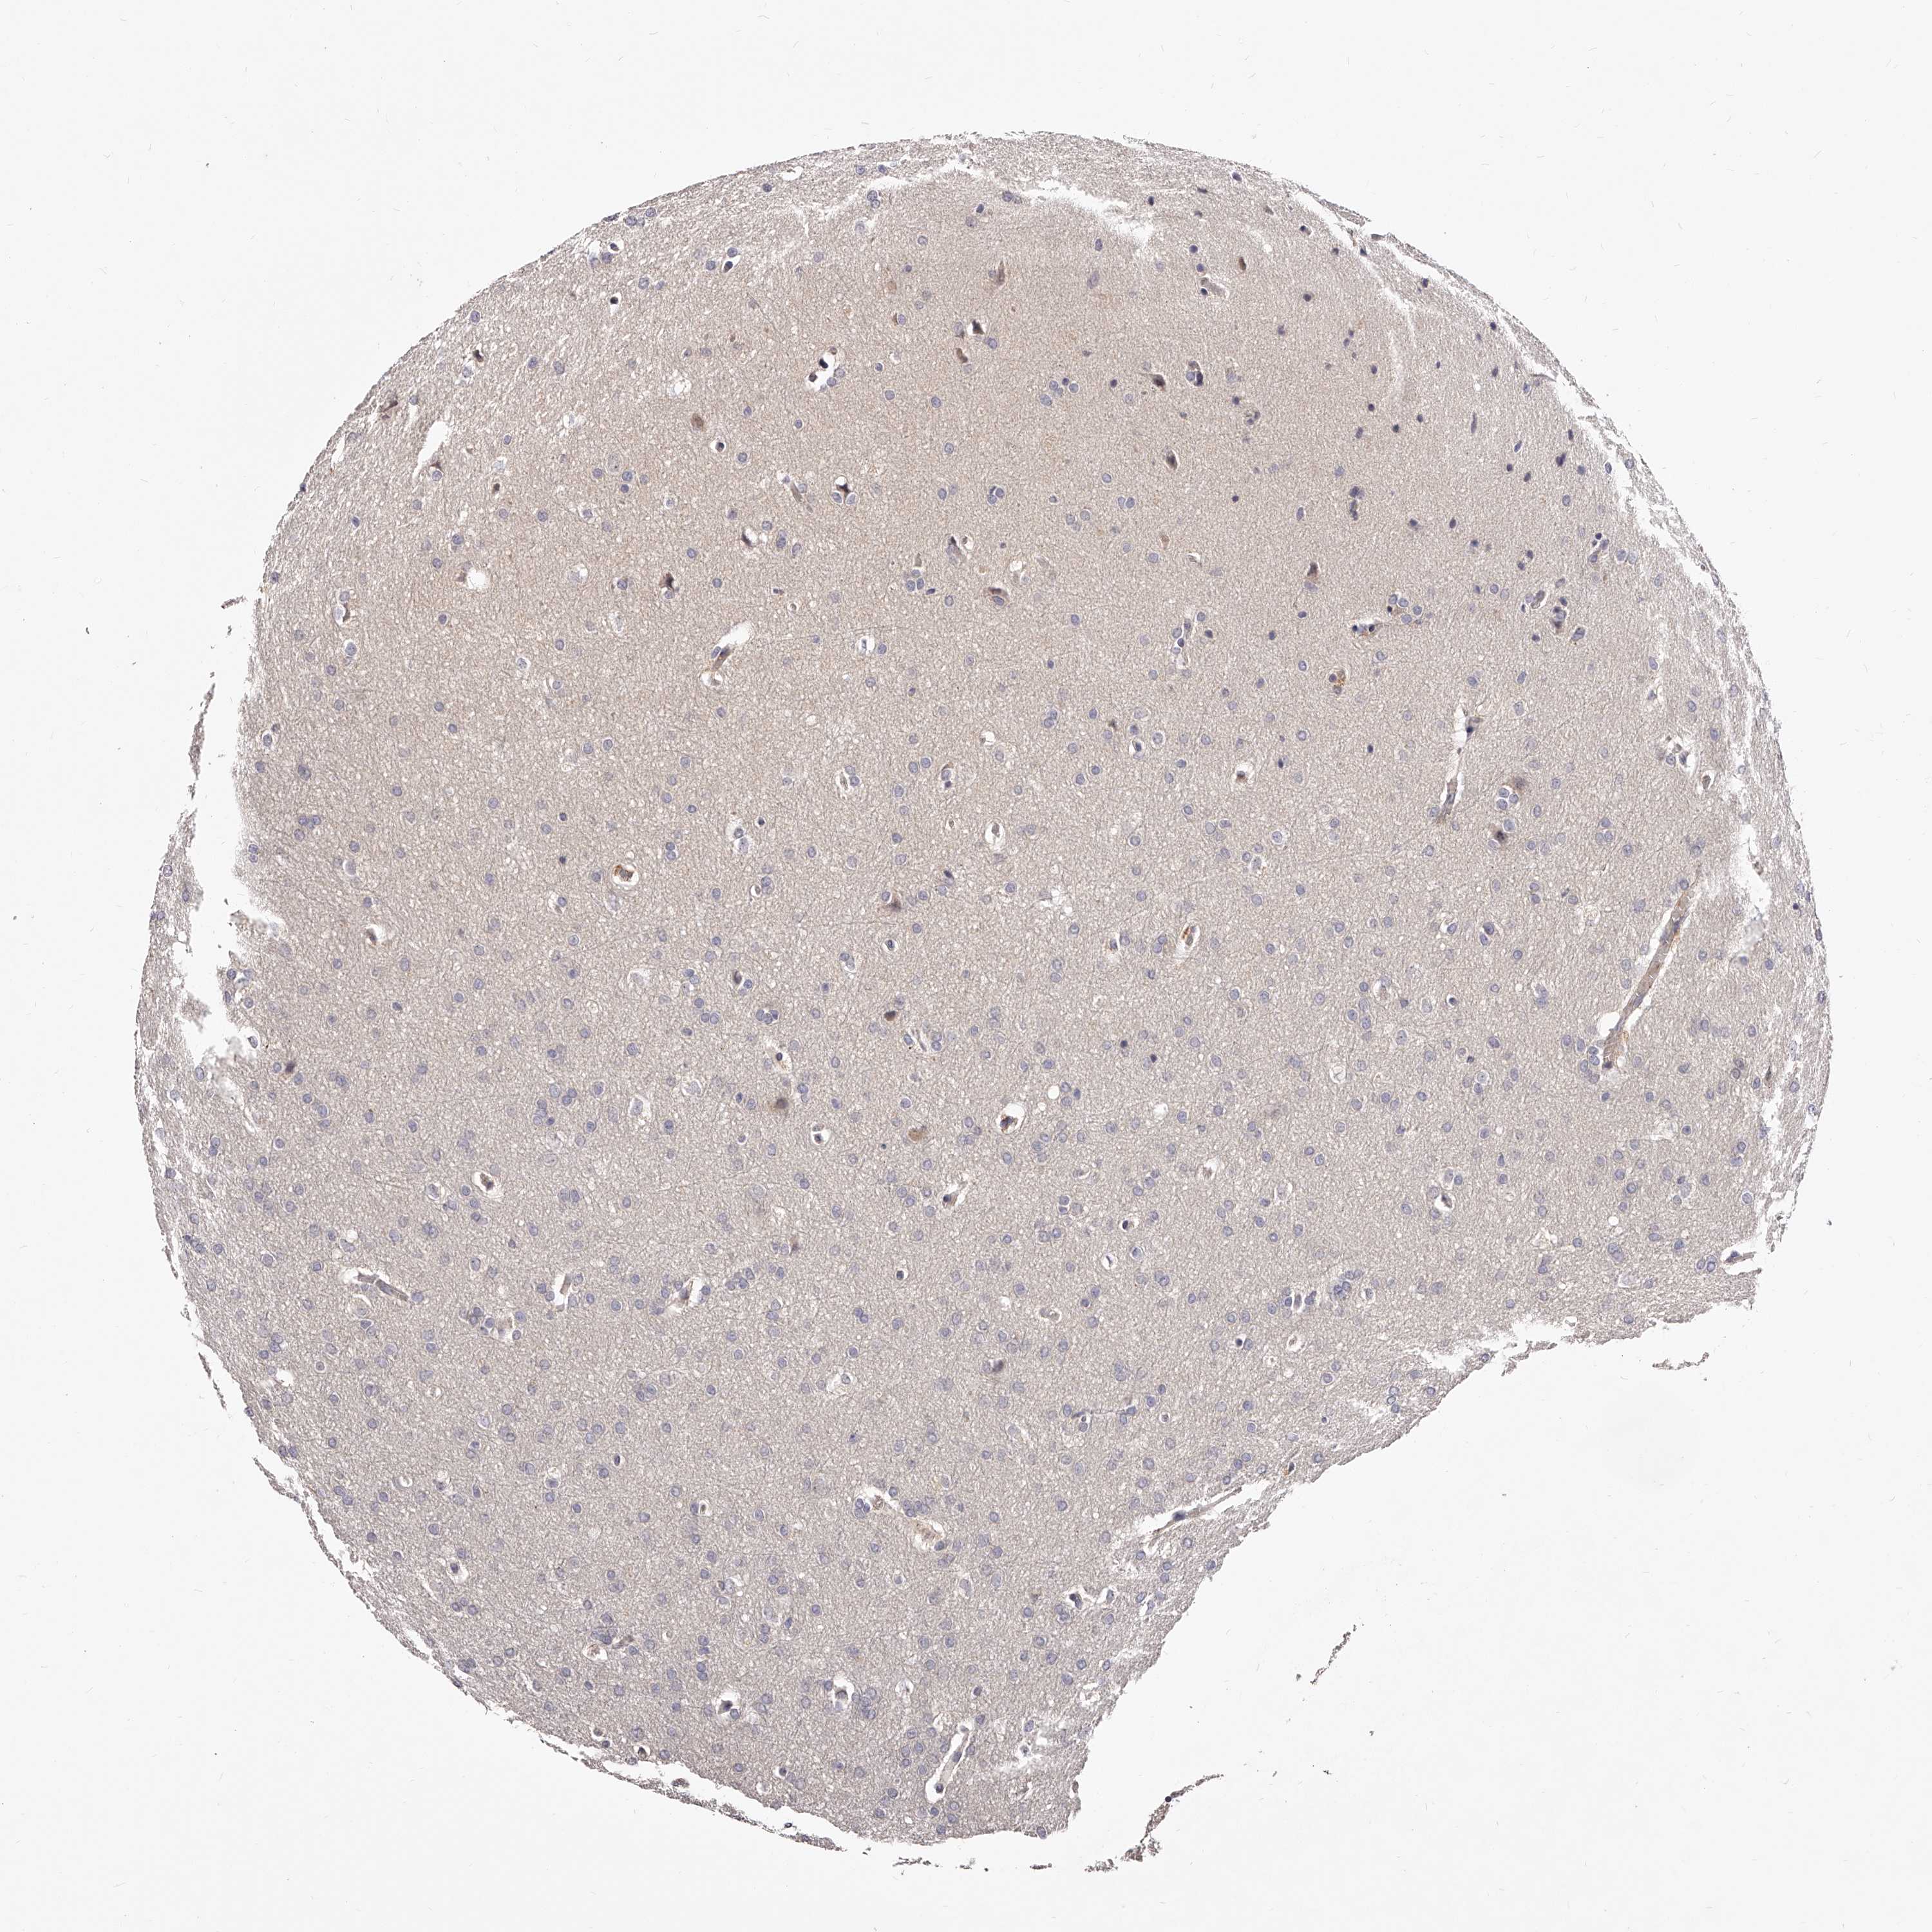

GLIOMA - Protein expressioni

A mouse-over function shows sample information and annotation data. Click on an image to view it in a full screen mode. Samples can be filtered based on level of antibody staining by selecting one or several of the following categories: high, medium, low and not detected. The assay and annotation is described here.

Note that samples used for immunohistochemistry by the Human Protein Atlas do not correspond to samples in the TCGA dataset.

Antibody stainingi

Antibody staining in the annotated cell types in the current human tissue is reported as not detected, low, medium, or high, based on conventional immunohistochemistry profiling in selected tissues. This score is based on the combination of the staining intensity and fraction of stained cells.

Each image is clickable and will lead to virtual microscopy that enables deeper exploration of all samples and also displays staining intensity scores, fraction scores and subcellular localization as well as patient and tissue information for each sample.

Antibody HPA024761

Antibody HPA029557

Glioma, malignant, High grade

Glioma, malignant, Low grade